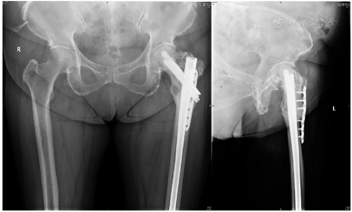

入院后完善检查,明确无手术禁忌证后,给予全身麻醉下行"左股骨粗隆下骨折骨不连髂骨取骨植骨内固定术"。手术方法:患者取仰卧位,左侧臀部垫高,常规消毒铺巾。沿原切口切开并适当延长,依次切开皮肤、皮下组织及深筋膜,钝性分离股外侧肌,显露并探查骨折断端,可见骨赘增生,骨折间隙纤维软组织充填。清除骨折间隙瘢痕组织,髂骨取骨修剪成颗粒骨充填,应用7孔锁定接骨板加强固定。手术时间2小时,出血约200 ml。术后安返病房。交待患者停用双膦酸盐,改用特立帕肽,20μg/支,每日一次,每次一支,皮下注射。患者在术后1年实现骨折临床愈合。

患者常规在术后1、3、6及12个月共随访四次,在术后第12个月骨折临床愈合,左髋行走后不再疼痛,实现完全负重行走。